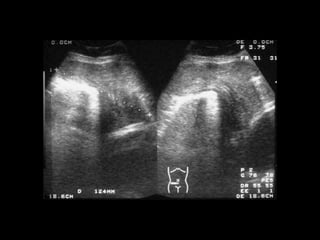

Diagnóstico

• USG: Área libre de ecos, que está ocupada por tejido

conectivo, y se puede ver un eco fuerte si se encuentra

el intestino en contacto con el orificio herniario

• En caso de adherencias, la apo de Spiegel y el tejido

adherido tienen casi la misma intensidad ecográfica, lo

que puede confundir

• TAC: Permite identificar los músculos que constituyen

la pared abdominal anterior y el transverso del

abdomen, así como el contenido del saco herniario